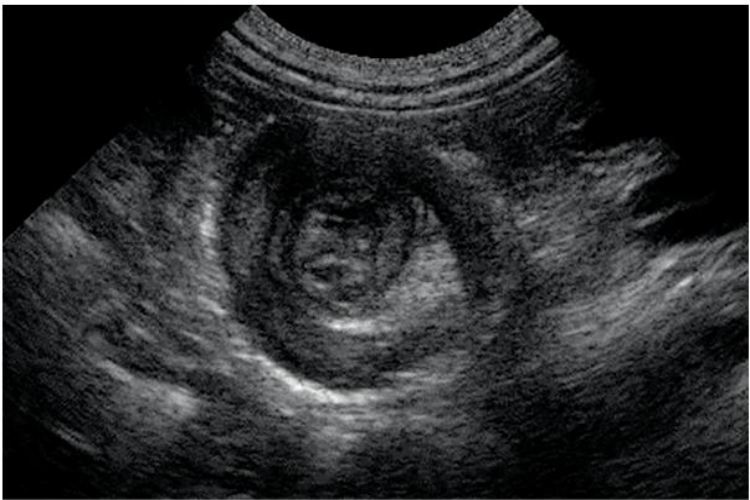

一般在肠梗阻发生4-6小时后腹部X线摄片可显示出肠腔内气体影,立位或卧位摄片可见液平面及胀气肠襻。有时空肠黏膜环状皱襞可显示“鱼肋骨刺”状,结肠梗阻时胀气位于腹部周边,显示结肠袋形。如液平面呈阶梯状,则提示小肠梗阻。如显示“同心圆”X线征象时,应考虑肠套叠。